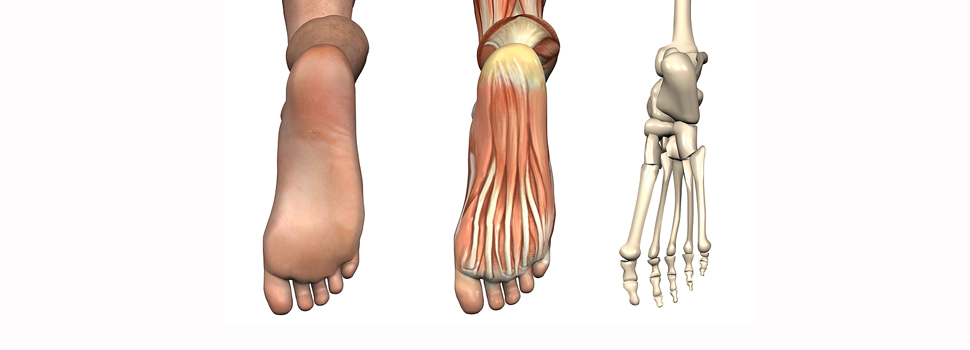

Podiatry

podiatry |pəˈdīətrē| noun the treatment of the feet and their ailments. Derivative:s podiatrist |-trəst| |pəˈdaɪətrəst| noun Origin early 20th century: from Greek pous, pod- ‘foot’ + iatros ‘physician.’ Like chiropodist.